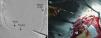

After the coronary sinus was accessed, venography showed the target lateral vein (Figure 1). The guide wire was introduced up to the distal portion of the vein and the left ventricular lead was advanced, but the proximal region of the vessel could not be crossed. It was decided to advance the guide wire from the lateral vein via a posterior collateral vessel up to the coronary sinus ostium (Figure 2). A snare system was introduced through a sheath via the left subclavian vein up to the atrium (Figure 3A) and the end of the guide wire was gradually pulled towards the skin surface. Thus, both ends of the guide wire were under the operator's control (Figure 3B) and the lead could be advanced to the desired position by pulling the guide wire (Figure 4). CRT parameters were satisfactory without diaphragmatic stimulation. There were no complications.